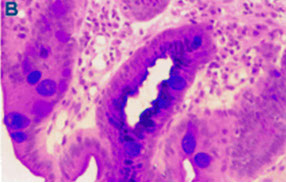

B) Incomplete IM or specialised columnar epithelium is differentiated from the complete IM subtype by the presence of goblet cells intermixed with mucin-secreting columnar-appearing non-goblet cells staining red and blue by the alcian blue (pH 2.5)-periodic acid Schiff stain (B).

A) Complete intestinal metaplasia (IM) goblet cells stained red or blue by alcian blue (pH 2.5)-periodic acid Schiff (PAS) stain and by presence of absorptive non-goblet cells.